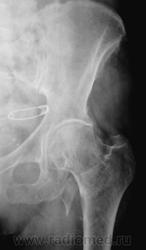

Пол пациента: Женский пол Тип патологии: Травма Область исследования: Скелетно-мышечная система Методы исследования: Rg Травма. Направлена на рентгенографию тазобедренного сустава https://radiomed.ru/sites/default/files/styles/case_slider_image/public/user/12/12.201201010053.jpg?itok=x97QZsTH ID:30719 Втр, 13/08/2013 - 18:18 #1 Sepsis Не на сайте Был на сайте: 1 год 8 месяцев назад Зарегистрирован: 13.12.2012 - 16:48 Публикации: 283 Отрывной перелом малого вертела. Втр, 13/08/2013 - 19:10 #2 Dima Не на сайте Был на сайте: 7 лет 2 месяцев назад Зарегистрирован: 05.08.2012 - 17:39 Публикации: 2467 По-моему черезвертельный с отрывом малого вертела Терпимость - это когда прощают чужие ошибки; такт - когда не замечают их. (Артур Шницлер) Втр, 13/08/2013 - 19:22 #3 maker4ik Не на сайте Был на сайте: 8 лет 7 месяцев назад Зарегистрирован: 19.10.2011 - 17:49 Публикации: 2682 Dima wrote: По-моему черезвертельный с отрывом малого вертела +1 Втр, 13/08/2013 - 19:50 #4 И.Бондаренко Не на сайте Был на сайте: 1 день 4 часа назад Зарегистрирован: 13.09.2011 - 22:55 Публикации: 9206 В основании шейки перелом, наверное чрезвертельный и отрыв малого вертела. Ср, 14/08/2013 - 13:20 #5 фатя Не на сайте Был на сайте: 4 года 2 месяцев назад Зарегистрирован: 13.02.2012 - 19:43 Публикации: 30 Чрезвертельный перелом с отрывом малого вертела фкар

Отрывной перелом малого вертела.

По-моему черезвертельный с отрывом малого вертела

В основании шейки перелом, наверное чрезвертельный и отрыв малого вертела.

Чрезвертельный перелом с отрывом малого вертела